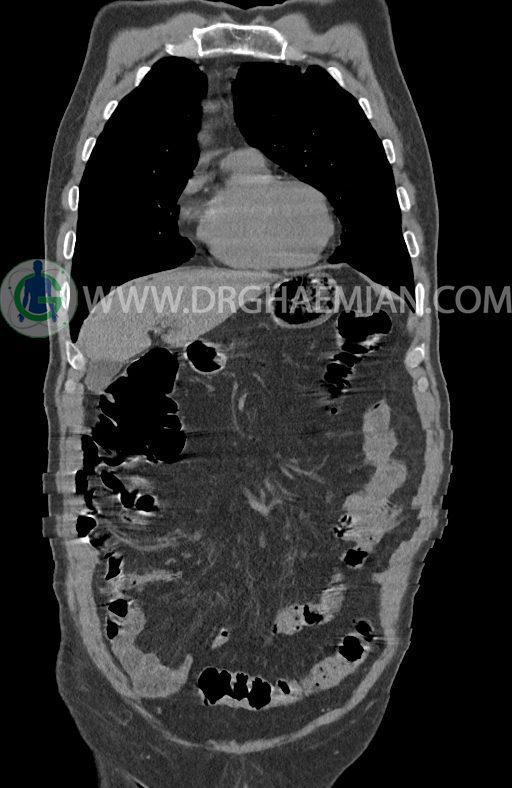

در سی تی اسکن اسپیرال ریه ها و مدیاستن، شکم و لگن با و بدون کنتراست وریدی (مولتی دیدکتور 16 با مقاطع ظریف و بازسازی کرونال) :

تراشه و برونش های اصلی نرمال اند.

پلورال افیوژن، جابجایی محتویات مدیاستن، کلسیفیکاسیون، کیست، فیبروز ریوی و Collection مشهود نیست.

حجم ریه ها، طرح برونکو واسکولر ریه ها، فیشر ها و هیلوم دو طرف طبیعی است.

–آتروفی نسبی پانکراس همراه با فوکوس های کلسیفیه ی منتشر پارانشیم مطرح کننده ی پانکراتیت مزمن

-CBD بسیار دیلاته (16mm) همراه با دیلاتاسیون مجاری داخل کبدی سنترال بدون شواهد سنگ یا توده در مسیر

–کیست های کورتیکال متعدد هر دو کلیه به بزرگترین قطر 56mm